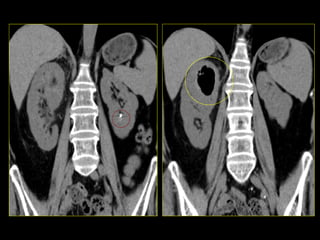

Caso # 2 ♀ , 6ta década de la vida  Estudio de TC para seguimiento y evaluación  de quistes renales.  Se realiza estudio con medio de contraste endovenoso, mostrándose la fase venosa, con cortes axiales y con reconstrucciones multiplanares (RMP) coronales.

Hallazgos Caso #2: Área hipodensa triangular en polo superior del riñón izquierdo, en relación con proceso inflamatorio lobar renal.